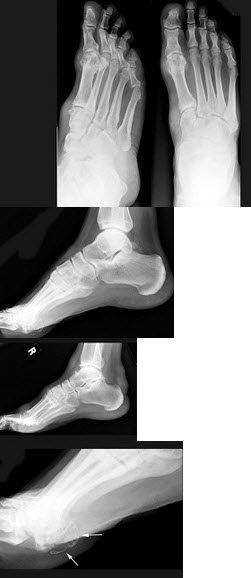

164、单项选择题

女,52岁,足跟痛,手指运动僵硬,结合图像,最可能的诊断是()

A.骨质疏松症

B.骨脓肿

C.骨囊肿

D.骨折

E.类风湿关节炎